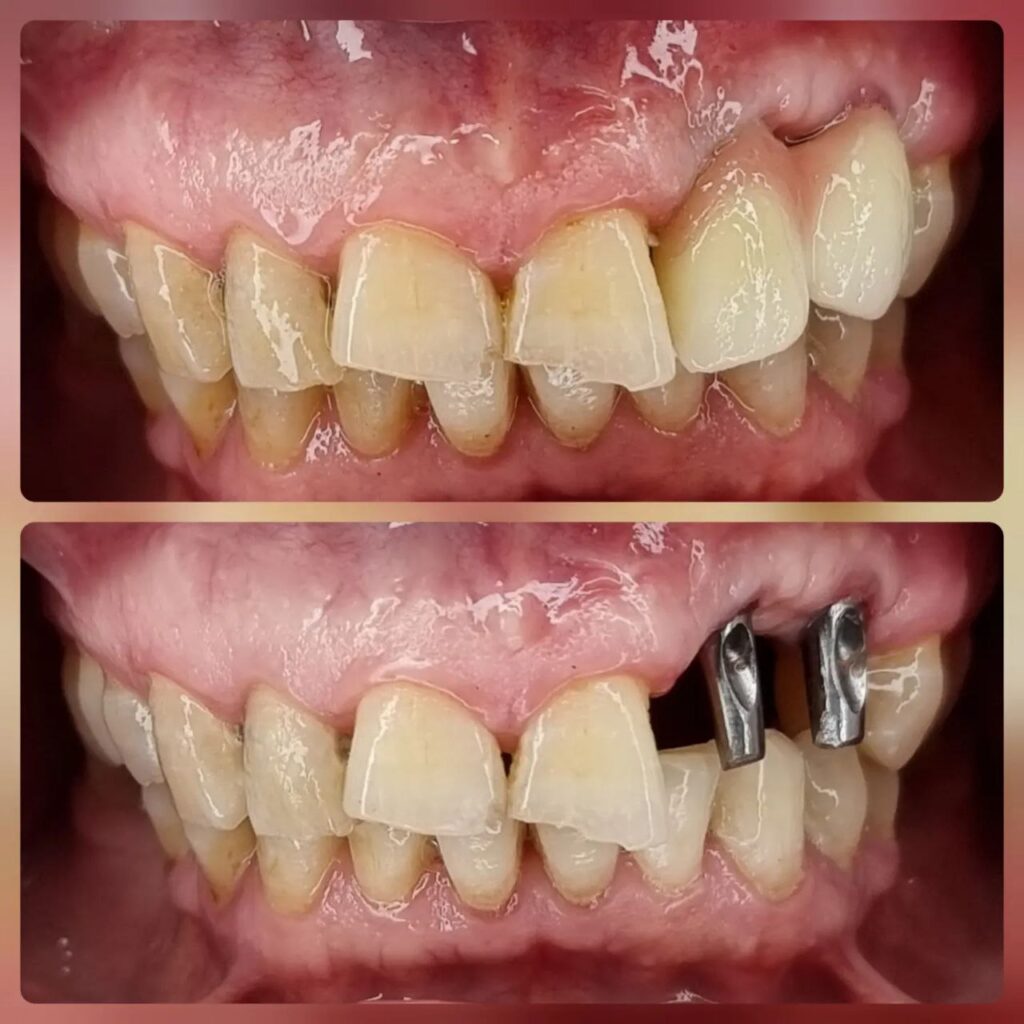

کاشت ایمپلنت دندان

اطمینان حاصل کردن از اینکه دندانهایتان به نحوی زیبا و طبیعی جایگزین شدهاند، از اهمیت بسیاری برخوردار است. ایمپلنت دندان به عنوان یک روش درمانی دائمی در دندانپزشکی شناخته میشود که حاصل آن، یک دندان زیبا و طبیعی در دهان شما خواهد بود.

هرچند که این روش درمانی هزینهی بیشتری نسبت به روشهای دیگر دارد، اما ارزش زیبایی که ایجاد میکند، قابل انکار نیست. ایمپلنتها به قدری شبیه به دندانهای طبیعی هستند که به سختی میتوان آنها را از دیگر دندانها تشخیص داد.